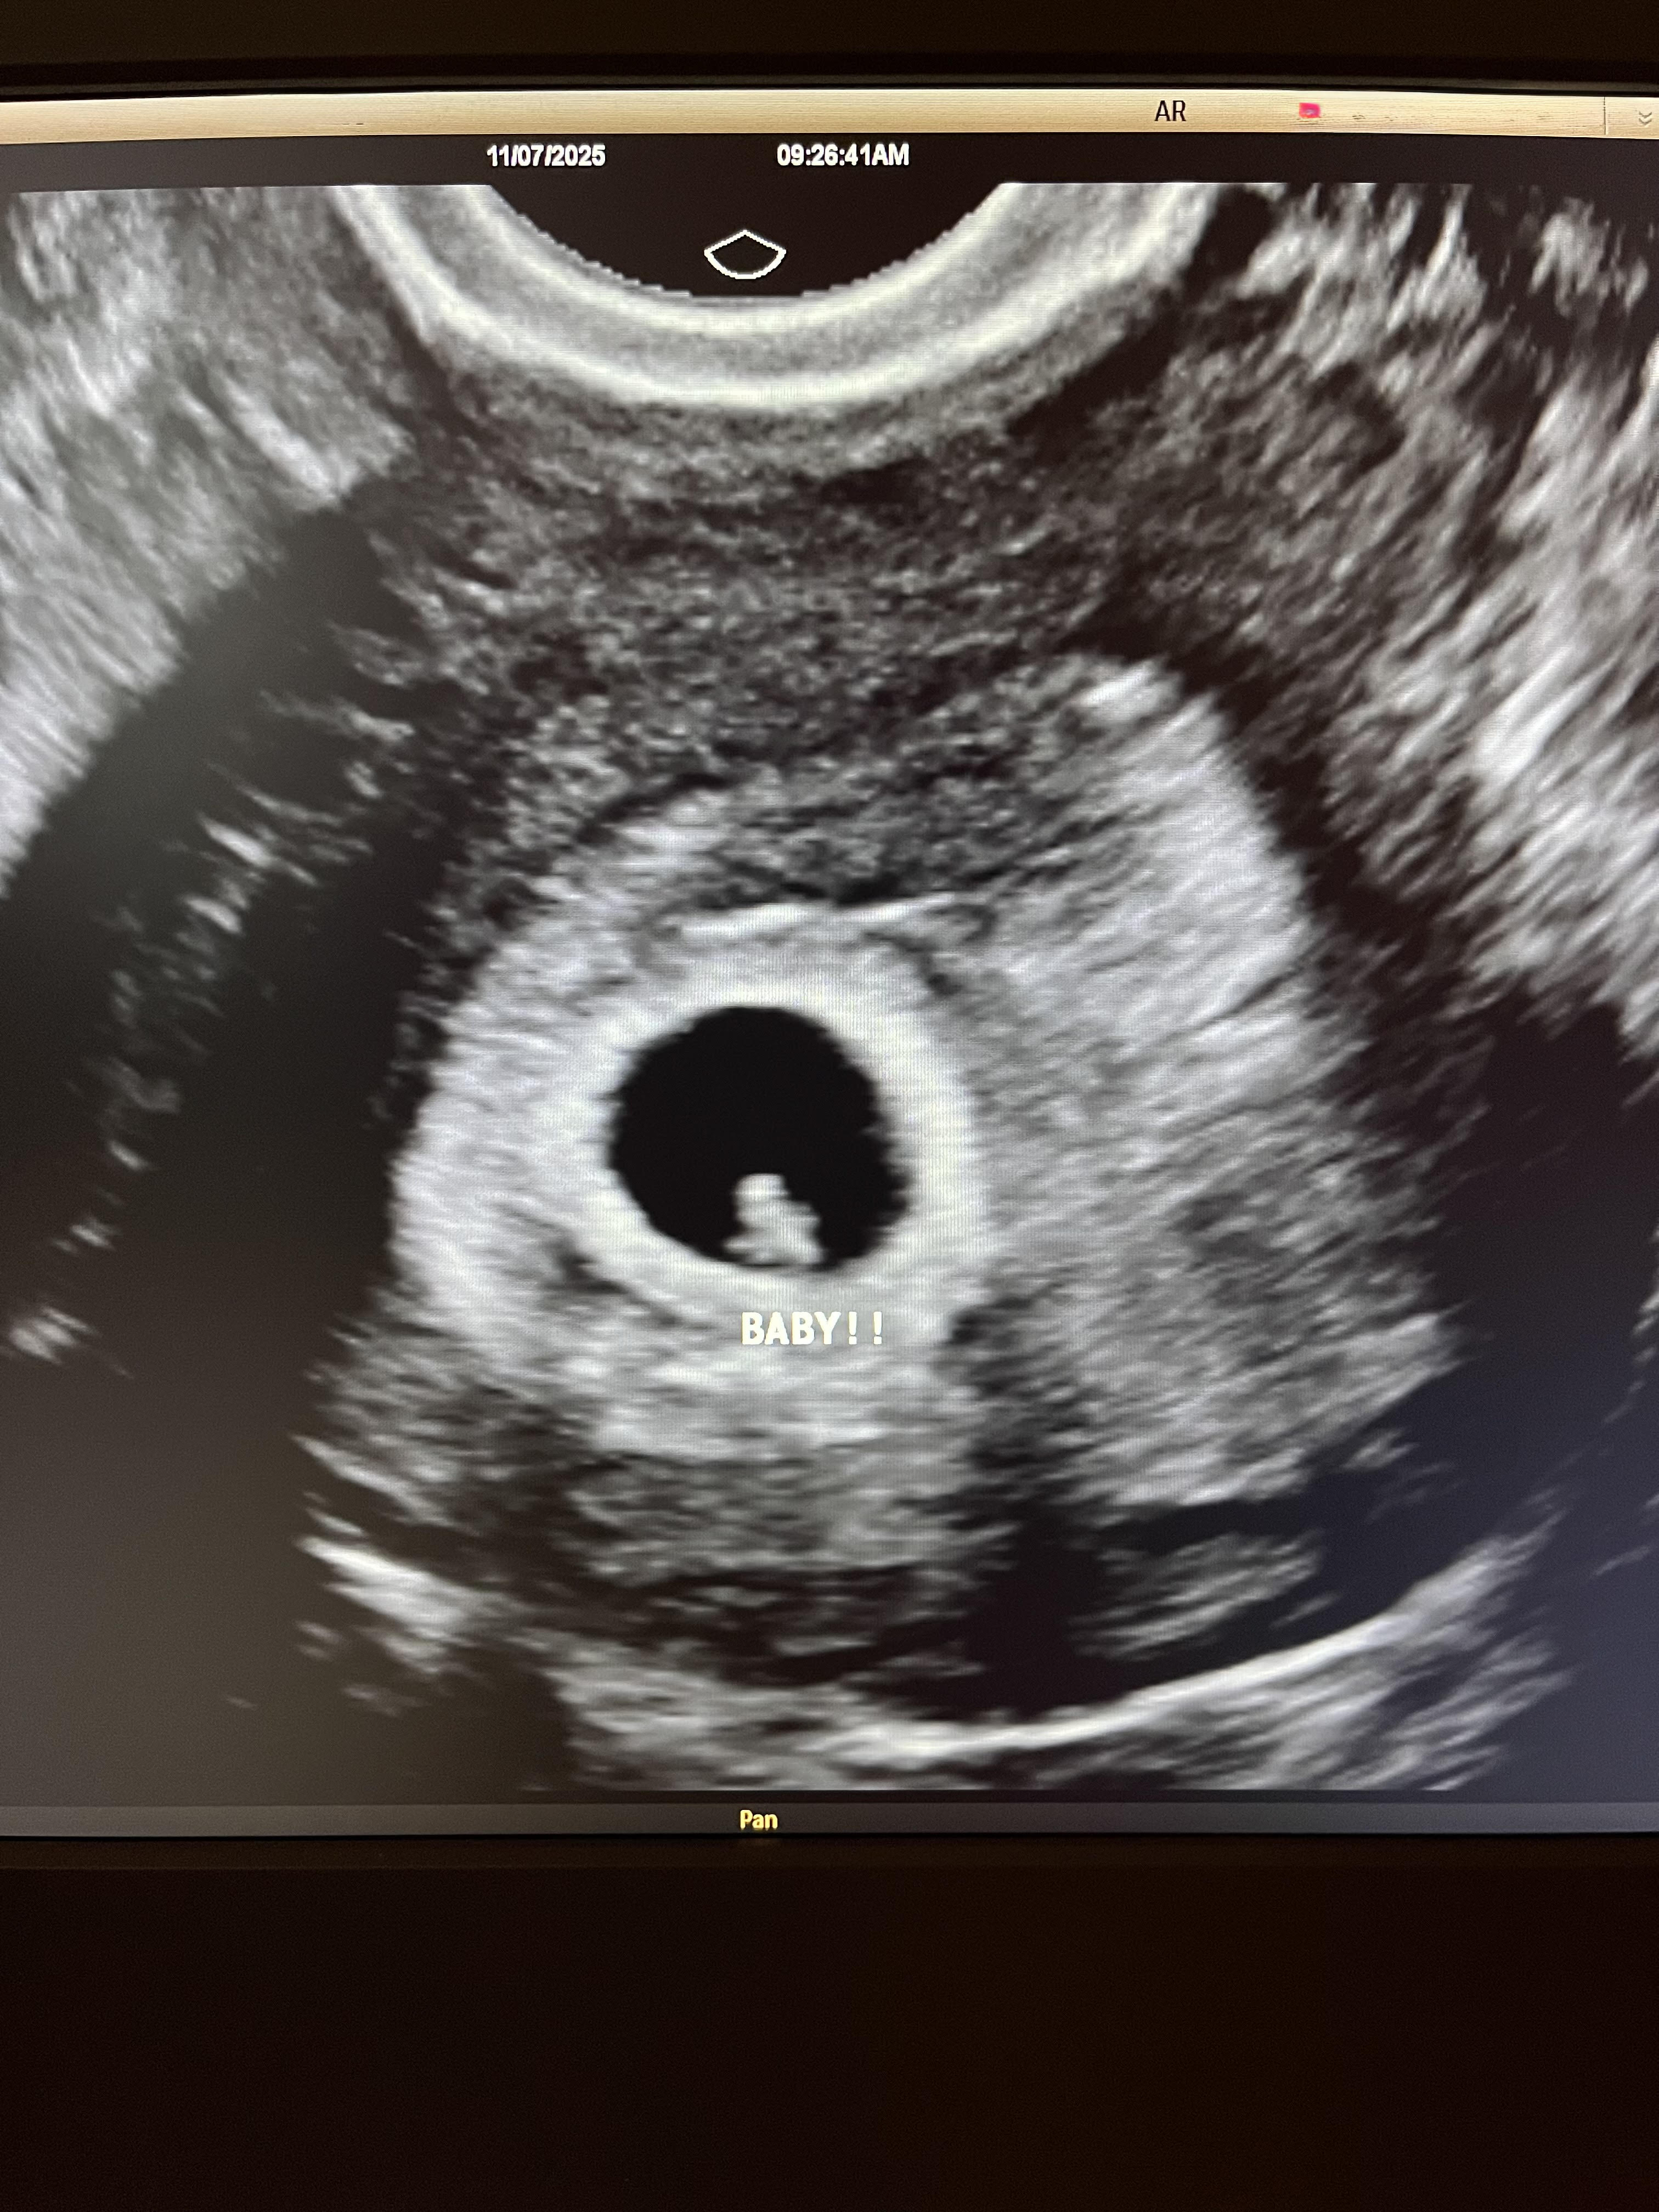

That process took about a month. We were supposed to move forward with the embryo transfer shortly after, but she actually tore her ACL and needed surgery, so that delayed things. Even with the delay, we stayed committed to working with her because she’s such an incredible person. Once we knew she was the right match, we were willing to wait. Her first embryo transfer happened in July. Unfortunately, that resulted in a miscarriage, which was really difficult.

Payments are structured around milestones—when a heartbeat is detected, and again at later stages of the pregnancy. And if there are complications during birth, there are additional costs associated with that as well.

[At the time of this interview], our surrogate is 22 weeks pregnant, so we’re about halfway through. It’s definitely been a process emotionally. She actually had the flu last week and had to be hospitalized. She called me in the middle of the night asking if it was okay for her to get a chest X-ray. I told her of course.